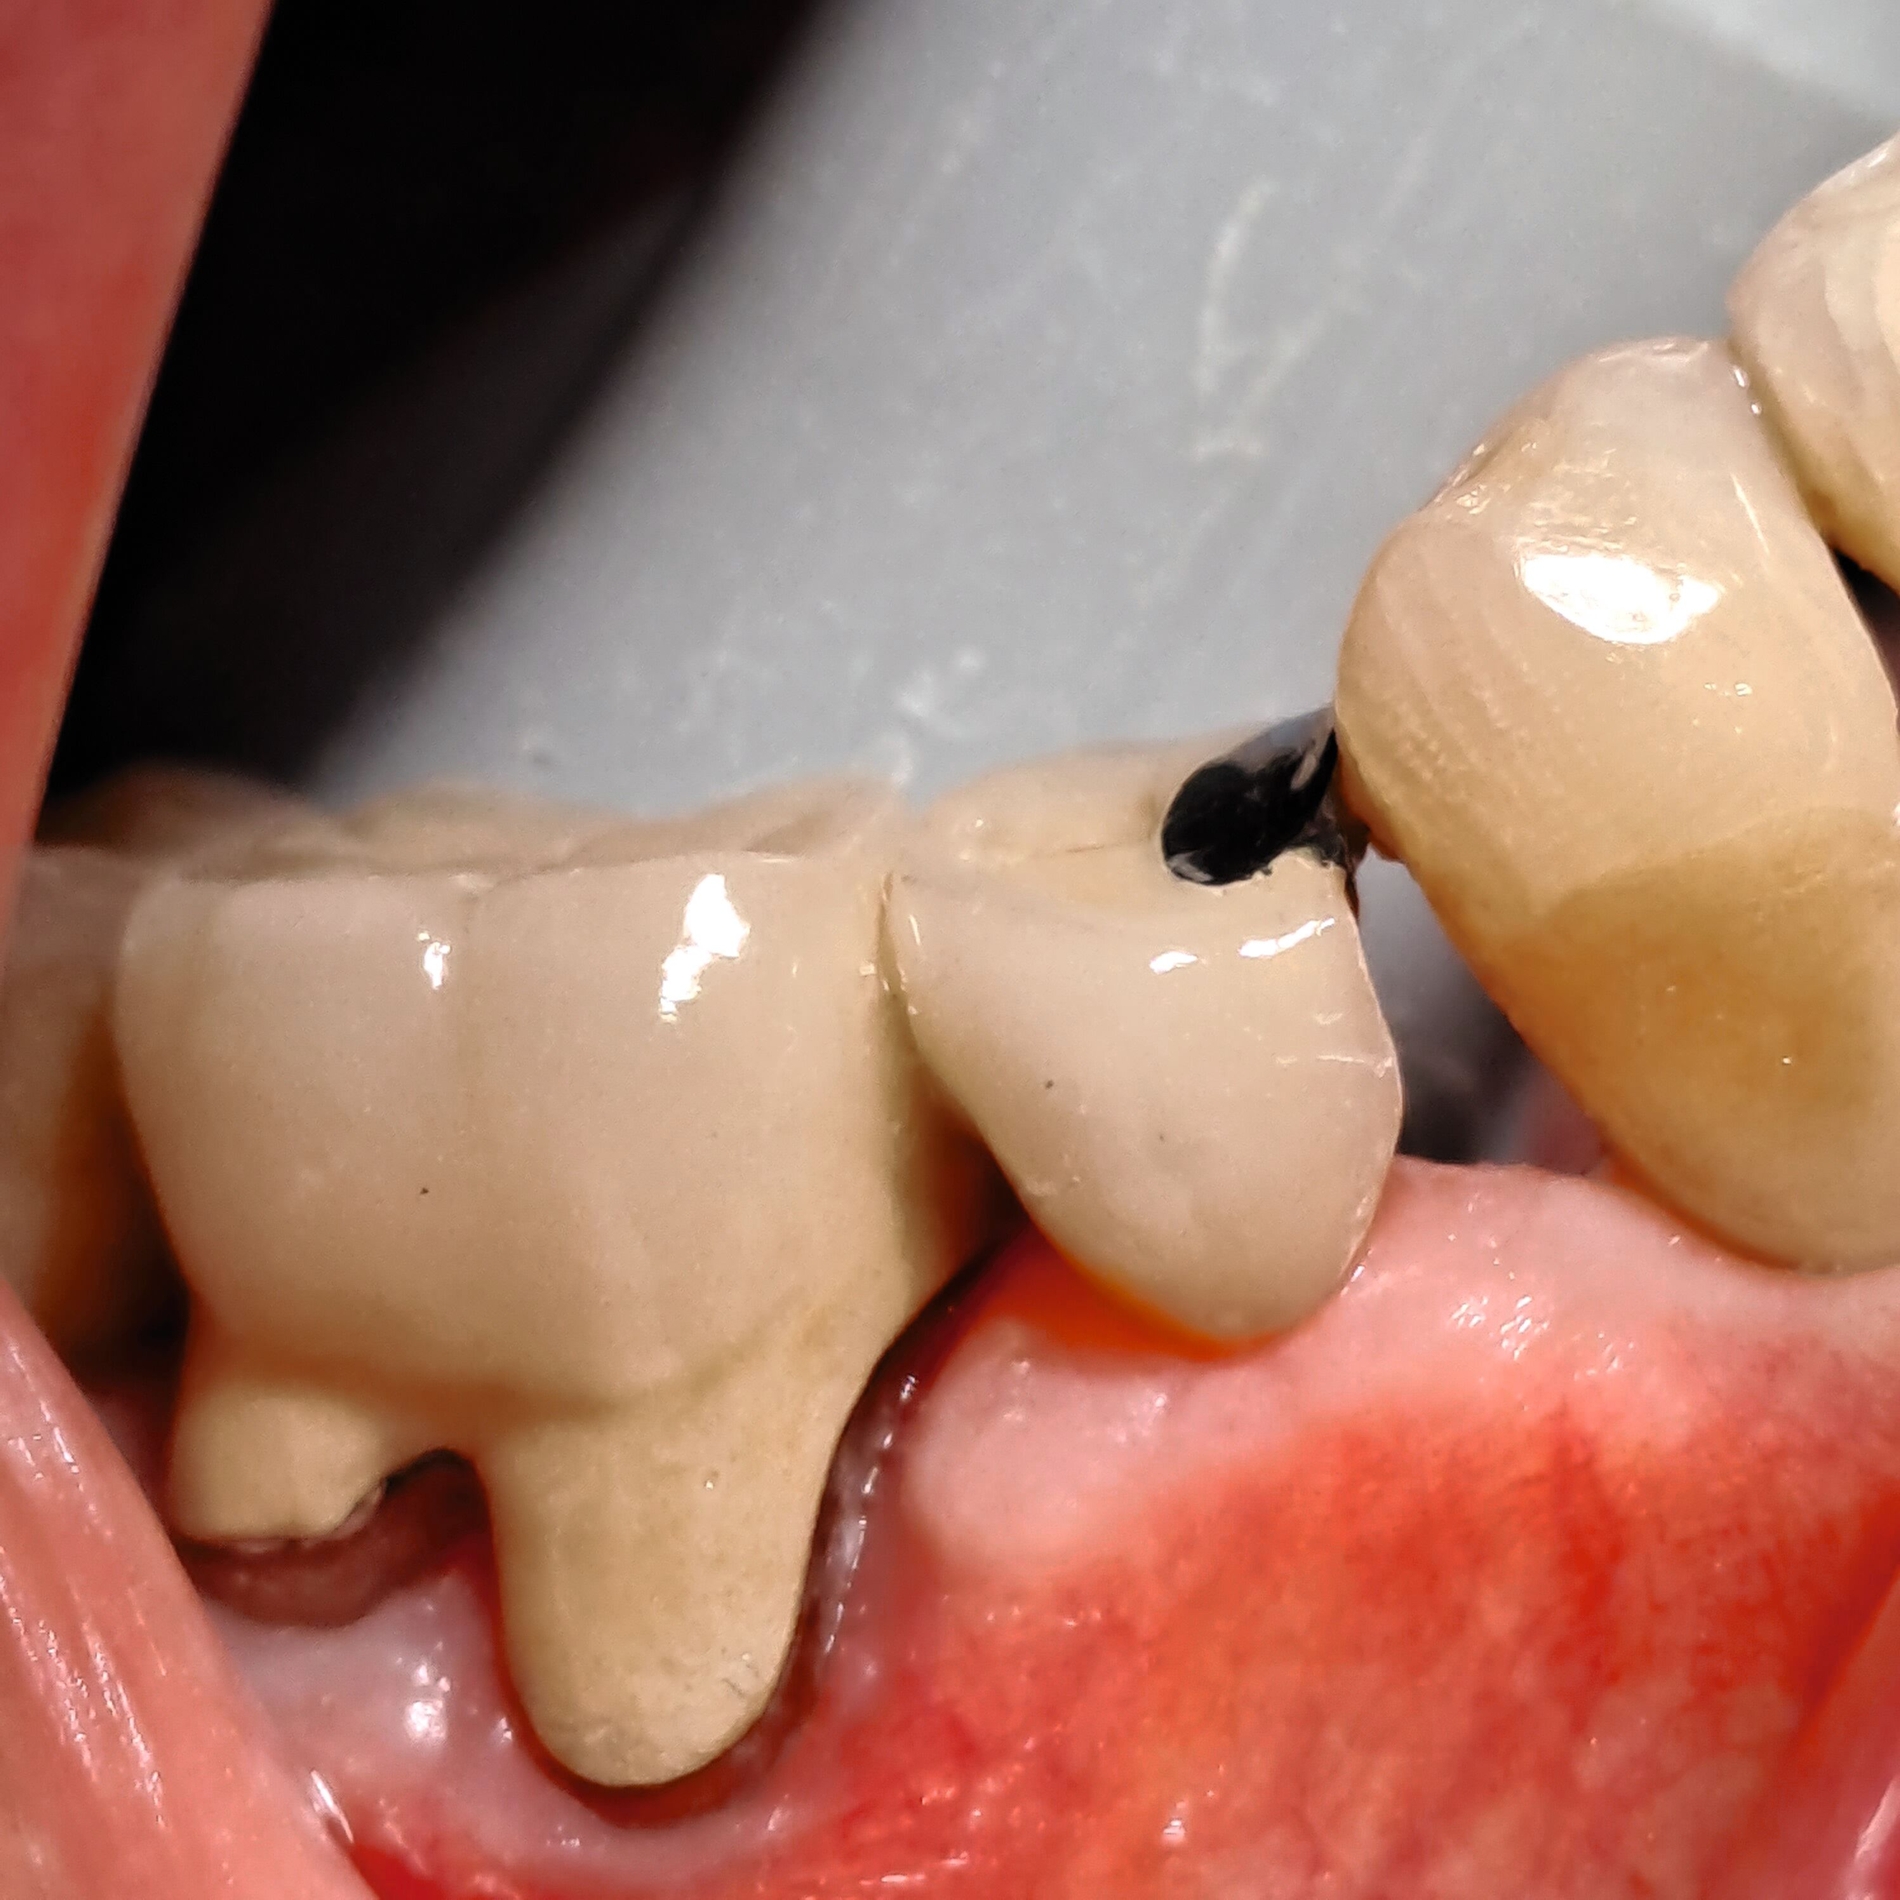

Die fertige Minibrücke besteht aus:

dem zementierten Anker (Krone oder Inlay), gegebenenfalls verblendet,

dem Brückenglied, in der Regel verblendet, und

der freien, metallischen Auflage auf dem Zahn jenseits der Lücke.

In den Abbildungen werden drei Fallbeispiele vorgestellt, bei denen alle Brücken noch in situ sind: